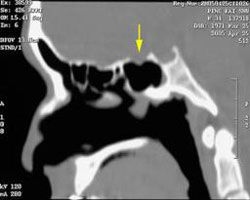

(三)鼻咽癌(nasopharyngedcarcinoma)外展神經在顱底前部被侵犯的原因以鼻咽癌最為多見,其次為海綿竇內動脈瘤及眶上裂區腫瘤。中年病人出現單獨的外展神經麻痹或同時有海綿竇征群的其它表現時,應首先考慮鼻咽癌的存在。常伴有鼻衄、鼻塞,可出現頸淋巴結腫大,作鼻咽部檢查、活檢、顱底X線檢查可確診。